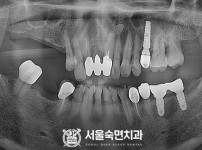

임플란트-전후사진3

치과를-선택할-때-꼭-확인하세요-서울숙면치과-임플란트-전후사진